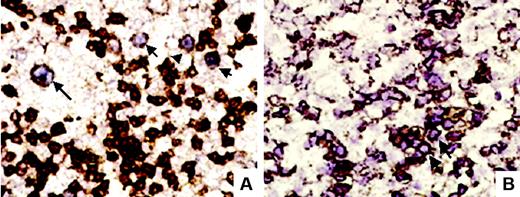

A semiquantitative, visual method was used to quantify the positivity of EBER-ISH. EBER-ISH–positive cases were classified into 4 categories (Figure 1A): Cases quoted as 1 showed only rare, less than 1% scattered positive cells; those quoted as 2 showing obvious, although scattered (1% to 5%) positive cells; those quoted as 3 showing numerous (5% to 50%) positive cells; and those quoted as 4 showing homogeneous positivity in more than 50% of cells.

Estimation of EBER expression level with spline curve. (A) Four-level semiquantitative estimation of different levels of EBER expression, quoted from 0 (EBER-ISH negative) to 4. Examples are shown at original magnification ×100 (top row) and ×200 (bottom row). Images were captured with a Zeiss Axioskop2 microscope (Zeiss, Oberkochen, Germany) and Neofluar 100×/0.1 NA optical lenses (Zeiss). Photographs were taken with a DP70 Olympus camera (Olympus, Tokyo, Japan). Image acquisition was performed with Olympus DP Controller 2002, and images were processed with Adobe Photoshop v7.0 (Adobe Systems, San Jose, CA). (B) The spline curve shows how the relative risk of death changes with the level of EBER positivity. The dotted lines show the 95% confidence interval. Bold lines show the best cut-off point.

Double-labeling techniques. (A) EBER-ISH and CD20 double-labeling showed in this case large CD20+ B cells (arrows) showing a purplish nuclear staining corresponding to EBERs (original magnification ×400). (B) In another case, EBER-ISH and CD2 double-labeling showed clusters (arrow) of CD2 and EBER-ISH–positive cells (original magnification ×400).